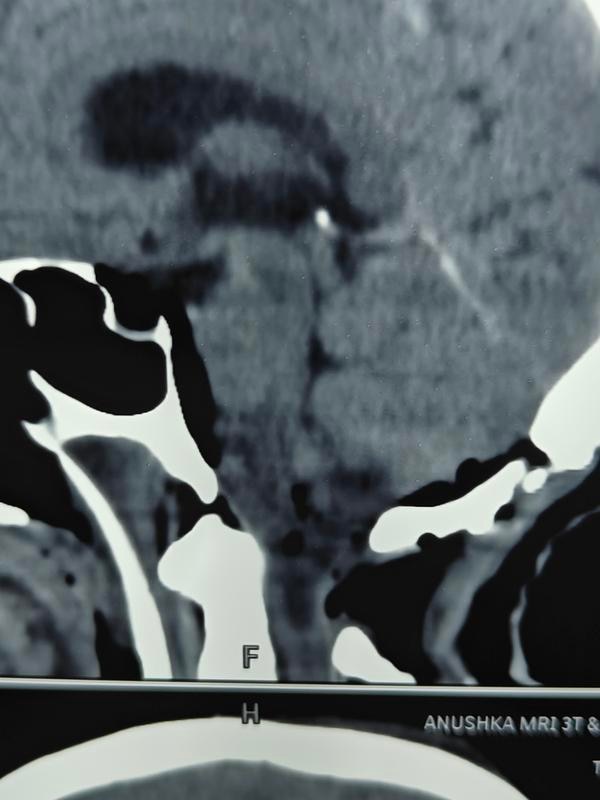

How serious is spinal surgery?Back surgery can carry higher risks than some other types of surgery because it is done closer to the nervous system. The most serious of these risks include paralysis and infections. Even with a successful surgery, the recovery time can be long.